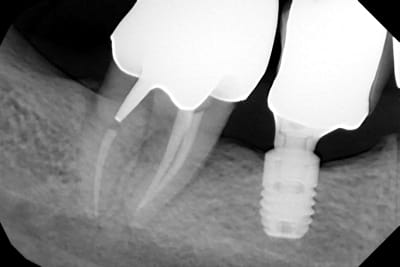

La radio est pas idéale…..mais bon il a une bonne gueule d’astra

https://www.spotimplant.com/fr/implants-dentaire/dentsply-implants/osseospeed-s